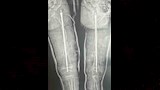

نجح فريق طبي بمستشفى سوهاج العام، في إجراء جراحة عظام كبرى لطفلة تبلغ من العمر 6 سنوات، مصابة بمرض العظام الزجاجية وكسر في عظمة الفخذ، وهي من العمليات الدقيقة والمعقدة؛ نظرًا لهشاشة العظام الشديدة التي يسببها المرض.

واستغرقت العملية نحو 3 ساعات، تضمنت إصلاح التشوهات بعظمة الفخذ وتثبيت الكسر باستخدام مسمار نخاعي متمدد ذاتي الإطالة، المخصص لحالات العظام الزجاجية.